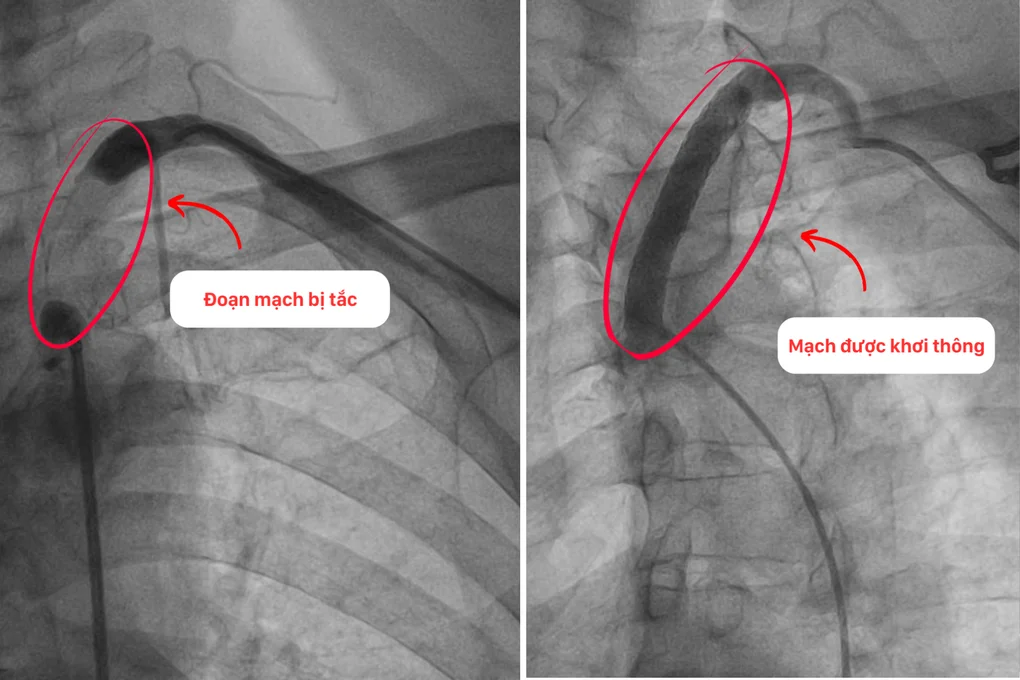

Đoạn mạch trước và sau can thiệp của ông Tài (Ảnh: BVCC).

Sau 1 tháng đặt stent động mạch vành phải, ông Tài bước vào lần can thiệp thứ hai, cũng là thử thách lớn nhất – đặt stent cho động mạch dưới đòn trái. Đánh giá về mức độ phức tạp trong ca can thiệp lần thứ hai này, THS.BS Nguyễn Văn Hải – Trưởng khoa Tim mạch – Tim mạch can thiệp BVĐK Hồng Ngọc Phúc Trường Minh cho biết: “Rất khó để đưa dụng cụ can thiệp vào tiếp cận vị trí động mạch bị tắc nghẽn do vị trí tắc nghẽn nằm gần gốc động mạch với nhiều mảng vôi hóa và xơ vữa. Nếu thao tác không chính xác sẽ dẫn tới nguy cơ bóc tách động mạch, thủng mạch bất cứ lúc nào”.

Nhờ vậy ê-kíp can thiệp đã thành công đặt 1 stent đặc biệt có kích thước lớn, độ bền tốt, chịu được áp lực cao khi vận động và có lớp màng bảo vệ phòng tái hẹp, giúp phục hồi lưu thông máu tới cánh tay cho ông Tài.